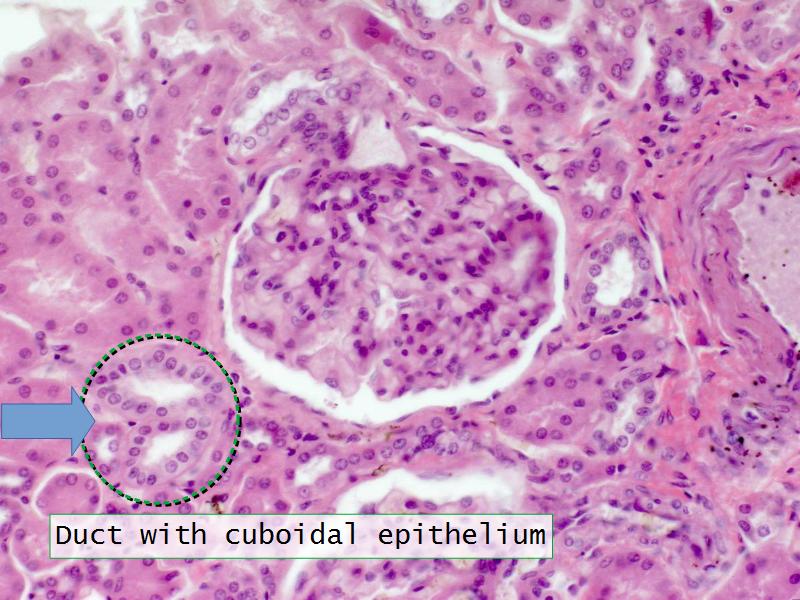

Slides 28 & 76

Kidney: Objectives

- Basic arrangement of nephrons and collecting tubules in the kidney

- Structure of the nephron and collecting tubules

- The renal corpuscle

- Make an annotated diagram of a nephron, including the juxtaglomerular apparatus. Indicate the flow of blood and water in each part, and how solutes are filtered, secreted and reabsorbed.

- Complete the drawings for each slide in the practical workbook.